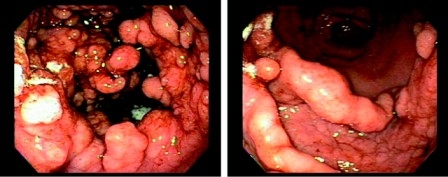

Большое значение в диагностике имеет рентгенологическое исследование. Изменения чаще наблюдаются по большой кривизне желудка: тело желудка, тело и синус, средняя и верхняя треть. Выявляется фестончатость и зазубренность контуров большой кривизны, грубые, утолщенные складки имитируют дефект наполнения как при опухолях, они ригидные, извилистые, неравномерно утолщенные, но сохраняют эластичность. Перистальтика сохранена. У 2/3 больных контуры желудка при контрастном рентгеновском исследовании остаются ровными, неизмененными. Стенка желудка, соответствующая поражению слизистой оболочки, эластична, перистальтирует. Другим важным методом диагностики гипертрофического гастрита является эндоскопическое исследование (ЭГДС) с использованием методики контроля давления в желудке при его раздувании. К гигантским складкам относят те, которые не расправлялись при давлении в желудке более 15 мм рт. ст. Визуально при болезни Менетрие складки резко утолщены, в виде мозговых извилин или «булыжной мостовой», легко ранимы, с эрозиями, геморрагиями, много слизи. Толщина складок не менее 2 см. Гистологическое исследование биопсионного материала не всегда дает характерные признаки болезни Менетрие - аденоматозно-кистозную гиперплазию желудочных желез. Выявляются различные формы хронических гастритов, иногда неизмененная слизистая. Однако биопсия позволяет дифференцировать гиперпластический гастрит от опухолевых поражений желудка.